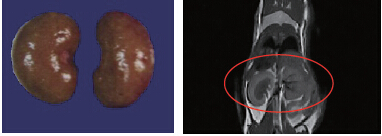

44.8g小鼠,肾脏体积:0.315cm3,解剖体积(水溢法):0.293cm3,成像时间:10min